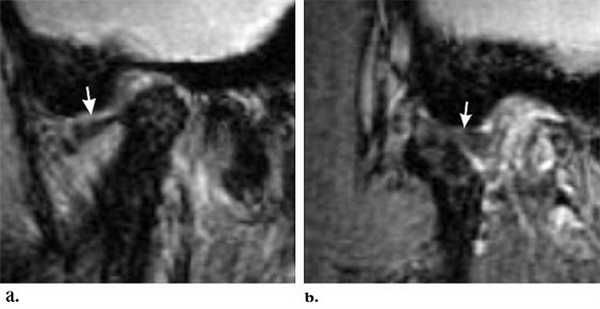

Перемежающийся (вправляемый) вывих /подвывих.

А. Закрытый рот. Переднее смещение диска.

Б. Рот открыт. Диск вернулся в нормальное положение между мыщелком и височной костью.

Фиксированный (невправляемый) вывих.

А. Рот закрыт. Переднее смещение диска.

Б. Рот открыт. Диск продолжает оставаться смещенным.